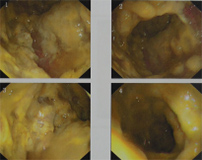

我科室治疗伪膜性肠炎患者1例对照,经7次高压氧治疗患者腹痛、腹泻症状明显好转,肠镜基本恢复正常。

治疗前

治疗后

治疗机制:1、高压氧作用下,血氧分压及组织氧分压增高,并促进新生血管形成使缺血缺氧组织的血供、氧供得到改善。2、高压氧可以改善损伤肠管的炎症。